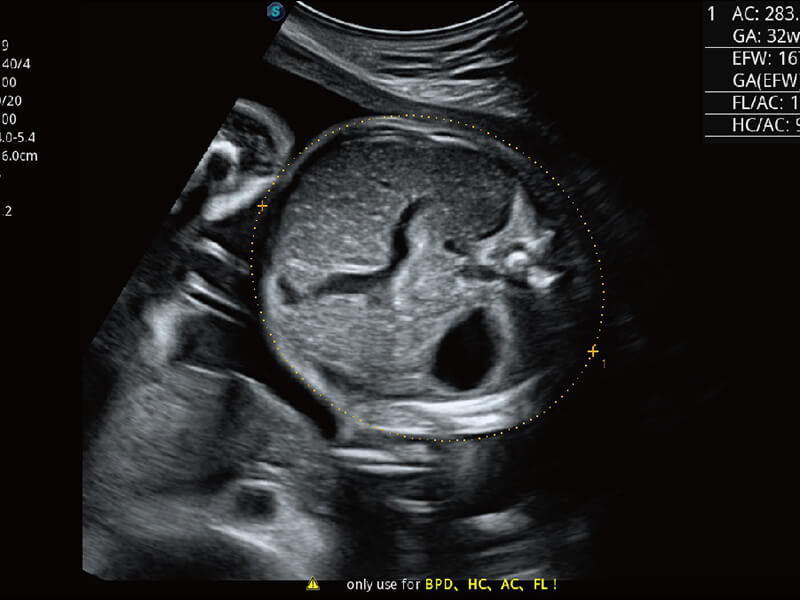

成像功能

S60探头工艺,从前端信号处理每一个环节采集无损声学数据,真实还原组织原貌,再现解剖细节。

超宽频带技术,为容积成像带来优质的二维图像基础,为您呈现丰富的结构细节,栩栩如生地展示宝宝的宫内形态以及各种组织的立体结构。